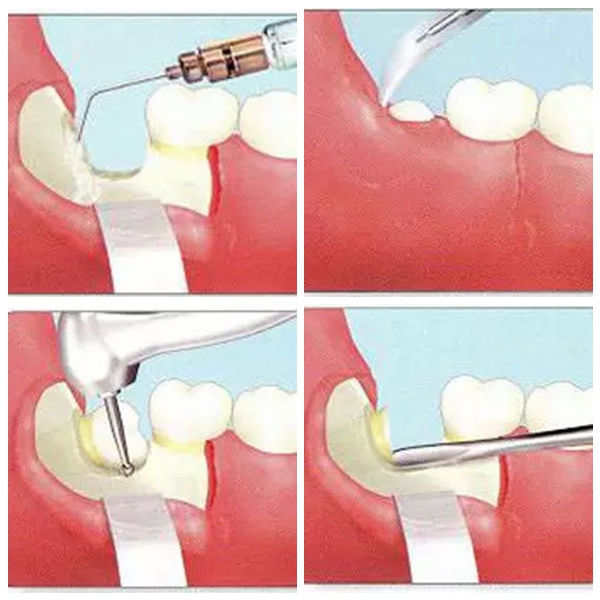

因為(wei) 拔牙會(hui) 在牙床上留下縫合的小創口,一般縫合後,會(hui) 有出血、創口輕微疼痛的情況是正常的。每個(ge) 人因為(wei) 體(ti) 質不同,所以存在很大的差異,有的人有不適,但是有的人沒有,一般拔牙後可以使用冰袋或者冰的毛巾來冷敷止疼消腫。一般幾天後就會(hui) 消除。還有注意拔牙後當天不要刷牙漱口,而且拔牙後會(hui) 有唾液明顯增多的情況,也不要拚命的吮吸和吐口水,以免引起創口的凝血塊被破壞而出血。

其實拔智齒看似事小,實際上需要了解的情況很多,建議要拔智齒的**提前谘詢醫生了解詳細情況。還有拔牙前不要空腹,要吃東(dong) 西,以免沒有體(ti) 力,還有月經期以及智齒發炎疼痛期是不能馬上拔牙的,這是大家需要知道的。